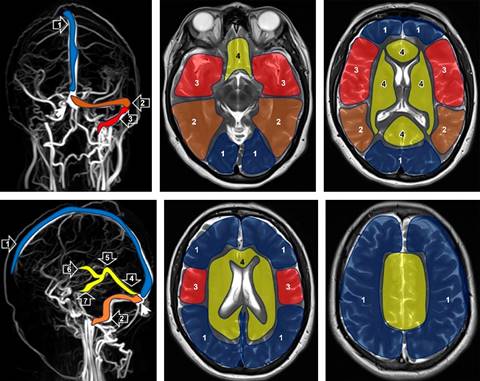

El diagnóstico se realiza mediante resonancia magnética (RM) en combinación con venografía-RM (Figura 1), una técnica no invasiva que permite identificar el trombo venoso y los cambios en el parénquima cerebral.3-5 El uso de heparina y anticoagulantes orales se basa en la reversión del proceso trombótico y prevención de complicaciones, mejorando notablemente el pronóstico de la TVC en los últimos 30 años.2,3,5

Figura 1: Representación en la venografía obtenida con un resonador magnético superconductor de 3T, mostrando los senos durales y venas superficiales y profundas, junto con sus respectivos territorios de drenaje. 1: seno sagital superior; 2: senos transversos; 3: senos sigmoides; 4: seno recto; 5: vena de Galeno; 6: venas cerebrales internas; 7: venas basales de Rosenthal; prensa de Herófilo o tórcula (punta de flecha).